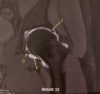

Which letter demonstrates the cervical nerve root exit foramina?

C

What letter demonstrates the intervertebral disc?

B

What letter demonstrates the conus medullaris?

A